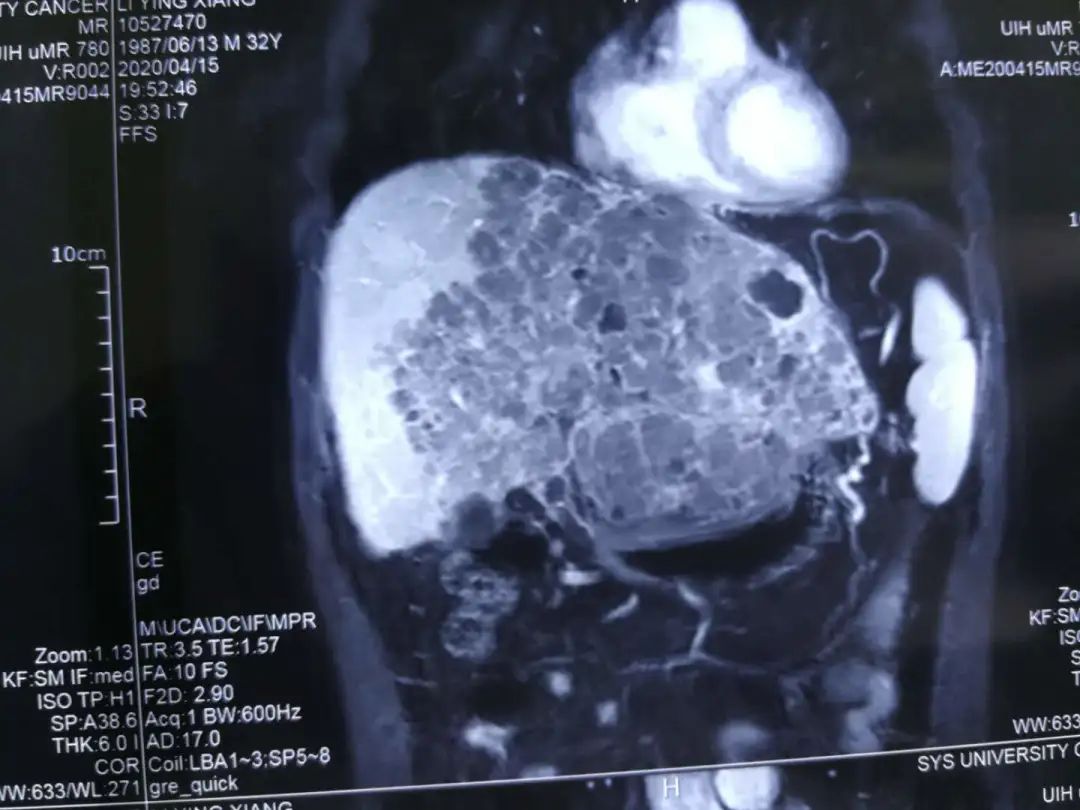

初次见到李先生的时候,他正坐在病床上,李先生看上去很精神,说话中气也很足。除却手上的吊瓶和身上的病号服,他看上去并不像一个肝癌症晚期病人。正值壮年的李先生今年32岁,是一名货车司机,然而在今年1月中旬李先生出现间或腹胀不适,还不间断发热,体温最高39.5度,他曾到当地医院诊治,以为是慢性胃炎于是开始对症吃药。因症状没有好转,2020年3月李先生又到市医院完善检查,行腹部超声示“肝内多发实性结节”,MRI检查示“肝左外叶及左内叶肿块、AFP 5630.26ng/ml”,考虑原发性巨块型肝癌,给予抗感染,护肝治疗后症状无明显好转。

“当时肿块差不多有14×10×6cm左右,但是不做手术可能活不过3个月。”当时医院建议他来广州看看,但一直发烧的他在疫情时期寸步难行,不仅挂号难、住院难,治疗也难,李先生来到广州一家大医院就诊竟然被告知说查不明白发烧的原因,只是给予抗病毒、护肝、抗感染、退热等对症支持处理,但仍有反复发热,最高至38.6度,并未行进一步抗肿瘤治疗。

“因为没有积极性的治疗,我那时候的肿瘤从14公分长到20公分,一个月不到就长了6公分,并且体重下降得厉害,从150斤瘦到120斤左右。”病情加重的李先生在一个做医生的亲戚介绍下,在2020年4月20日来到广州复大肿瘤医院就诊。刚来医院的第一天,牛立志院长特定来看李先生并对其病情进行诊断并告诉他:“肿瘤虽然严重,但你还很年轻,坚持治疗还是会有机会的。”